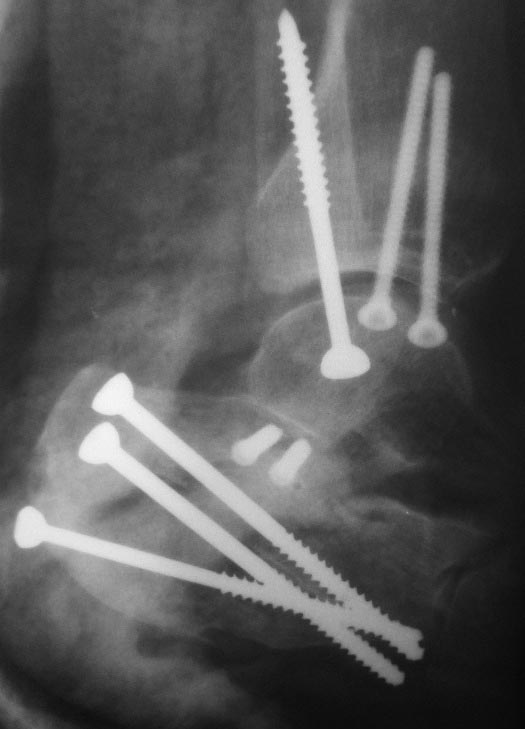

Р

2

3

Дополнительно дооперационная СКт